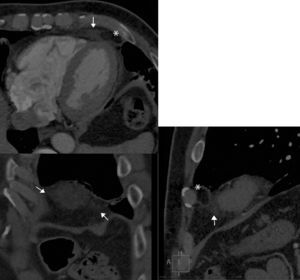

Varón de 57 años sin factores de riesgo cardiovascular ni otros antecedentes patológicos de interés, inició un cuadro de dolor torácico agudo sin claras características anginosas. Acudió al servicio de urgencias, donde el electrocardiograma y una primera determinación de marcadores de daño miocárdico resultaron normales. Se realizó una tomografía computarizada cardiaca, que descartó la existencia de lesiones coronarias. Sin embargo, en la grasa del ángulo cardiofrénico izquierdo (figura) se observaba un aumento de densidad mal definido (flechas), con una zona central de igual densidad que la grasa mediastínica (asterisco). En el interior de la lesión se observaba un discreto aumento de densidad en forma de filamentos finos. Estos hallazgos son los típicos de la necrosis de la grasa pericárdica. Se trata de una entidad poco frecuente, de características benignas, que clínicamente se manifiesta con dolor torácico de inicio agudo en personas previamente sanas. Su etiología es desconocida y las características anatomopatológicas son las mismas que las de la necrosis de la grasa en otras localizaciones (mama, apéndices epiploicos). El dolor se autolimita en pocos días, por lo que el tratamiento sintomático es suficiente.